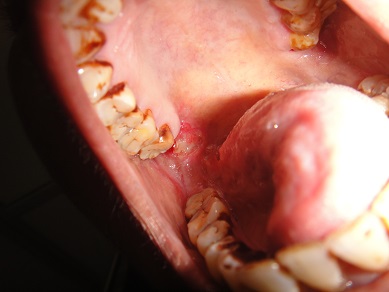

32 YEARS OLD MALE SUFFERING FROM RIGHT LOWER GINGIVO BUCCAL MUCOSA CARCINOMA INVOLVING RIGHT RETROMOLAR TRIGONE.PATIENT HAS ACTIVE PULMONARY TUBERCULOSIS.RIGHT RADICAL NECK DISSECTION WITH RIGHT DISTAL MANDIBULECTOMY WITH RIGHT LOWER ALVEOLECTOMY WITH RIGHT PECTORALIS MAJOR MYOCUTANEOUS FLAPE DONE.